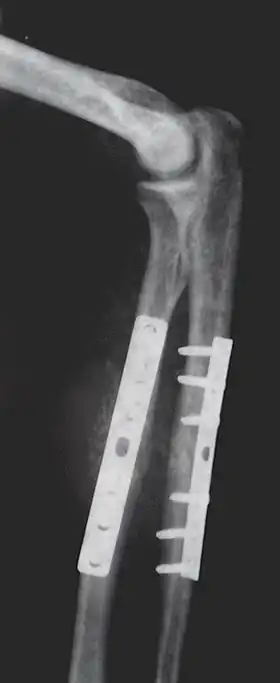

Internal fixation is an operation in orthopedics that involves the surgical implementation of implants for the purpose of repairing a bone, a concept that dates to the mid-nineteenth century and was made applicable for routine treatment in the mid-twentieth century.[1] An internal fixator may be made of stainless steel, titanium alloy,[2] or cobalt-chrome alloy.[3]

Closed reduction internal fixation (CRIF) is reduction without any open surgery, followed by internal fixation. It appears to be an acceptable alternative in unstable distressed lateral condylar fractures of the humerus in children, but if fracture displacement after closed reduction exceeds 2 mm, open reduction and internal fixation is recommended.[4]

Open reduction internal fixation (ORIF) involves the implementation of implants to guide the healing process of a bone, as well as the open reduction, or setting, of the bone. Open reduction refers to open surgery to set bones, as is necessary for some fractures. Internal fixation refers to fixation of screws and/or plates, intramedullary rods and other devices to enable or facilitate healing. Rigid fixation prevents micro-motion across lines of fracture to enable healing and prevent infection, which happens when implants such as plates (e.g. dynamic compression plate) are used. ORIF techniques often are used in cases involving serious fractures such as comminuted or displaced fractures or, in cases where the bone otherwise would not heal correctly with casting or splinting alone.